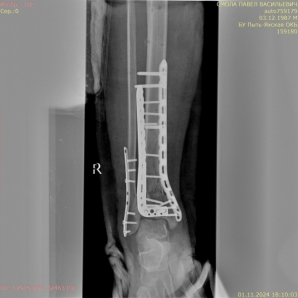

1) Мужчина, 35 лет. ДТП, водитель. Поступил в экстренном порядке. Диагноз — закрытый оскольчатый перелом дистального метаэпифиза правой большеберцовой кости, перелом наружной лодыжки правой голени со смещением отломков (рис. 1).

Рис. 1.

Ввиду выраженного отечного синдрома в области перелома была выбрана методика конверсионного остеосинтеза. На первом этапе были выполнены открытая репозиция, остеосинтез наружной лодыжки пластиной, фиксация голеностопного сустава аппаратом внешней фиксации (рис. 2).